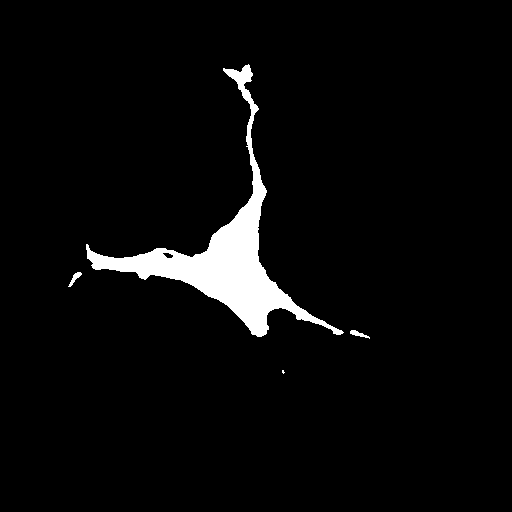

We evaluate the performance of each approach with five classical metrics: intersection over union (IoU), Dice score, precision, recall, and Hausdorff Distance (HD). We provide results on datasets , , and in Tables 1, 2, and 3, respectively. In Figure 2, we also illustrate representative segmentation results on dataset for each methods.

Raw

GT

U-net

CE-net

Attention U-net

AURA-net

The original U-net model produces poor segmentation results on datasets and while performing better on dataset . CE-net performs better than U-net and results in a strong recall in all three datasets. Attention U-net outperforms both CE-net and U-net on most metrics. The Attention gates incorporated in AURA-net allow outperforming CE-net, while its pre-trained layers help improve over Attention U-net. On top of that, the AC loss provides the network with additional information on object regions. As a result, AURA-net generally outperforms competing approaches. It occasionally scores closely to Attention U-net and CE-net, and even concedes a lead on recall in datasets and and on precision in dataset . It however performs best overall, with a consistent clear advantage on the IoU, Dice, and HD metrics.